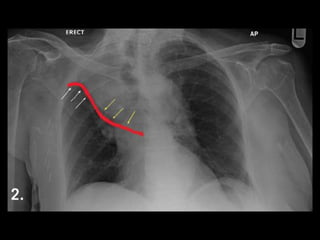

Squamous cell ca

Central Location (2/3)

Atelectasis

"Reverse S sign of Golden”

Post-obstructive pneumonia

May cavitate

Most closely associated with smoking